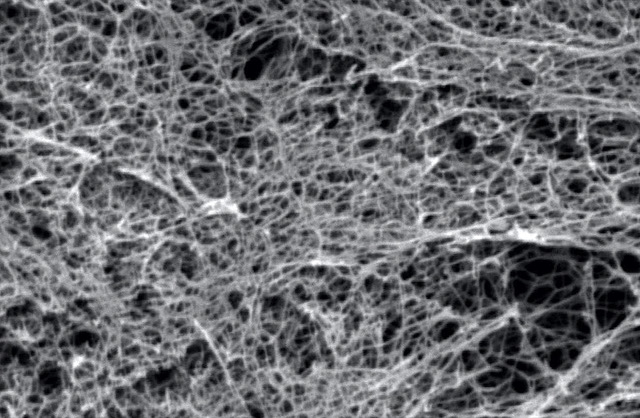

I peptidi auto-assemblanti (SAP) sono da tempo il fiore all’occhiello della nanomedicina internazionale applicata alla ricostruzione dei tessuti biologici grazie alle loro uniche qualità come biocompatibilità, purezza e versatilità.

Lo studio dimostra, per la prima volta, che ,con tali materiali interamente sintetici e progettati a livello molecolare in laboratorio, è possibile ottenere strutture cellulari nervose complesse. Le stesse sono dotate di attività elettrica e ottenute da cellule staminali neurali umane. Ciò consente di avere un modello di network di cellule nervose in laboratorio su cui testare futuri farmaci, minimizzando così la sperimentazione animale. E’ stato così costituito un primo “patch” nervoso (neuroprotesi) potenzialmente utilizzabile in clinica in futuro, utilizzando solo componenti già approvati in tal senso (es. cellule staminali neurali umane, materiali peptidici sintetici), evitando ad esempio ogni derivato animale. La neuroprotesi, fatta maturare in laboratorio e successivamente trapiantata in lesioni al midollo spinale, incrementa la rigenerazione nervosa. Tutto ciò dimostra come, grazie alla tecnologia dei peptidi auto-assemblanti, è possibile customizzare un biomateriale per la specifica applicazione.